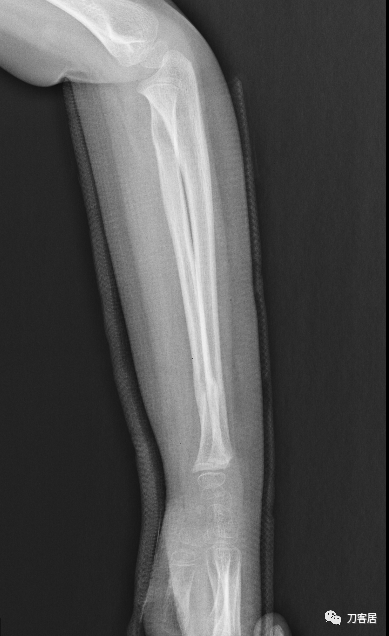

2021年7月22日晚,上海美华医院儿童骨科的师东良医生,给我提供了一例他处理的严重移位尺桡骨双骨折病例,经过手法复位,石膏外固定治愈。这个病例,其他医院建议要做手术。实际上,这样的病例,在现实中有太多太多,因为手法复位,石膏外固定治疗骨折,这是骨科医生的基本功。

下面为师东良医生提供的病例:

超声引导下闭合手法复位石膏外固定治疗7岁患儿尺桡骨远端移位双骨折。

男,7岁,左前臂远端桡尺骨双骨折,术前X光片见图1,行超声引导下闭合复位石膏外固定术,康复训练,6周拆石膏,随访2.5月的效果。术后2.5X光片见图23。功能上仅前臂旋后较健侧减小15°,继续加强康复训练中。家长满意,评价见图4